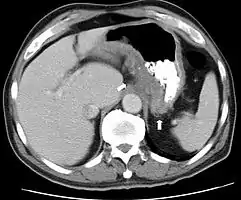

تصویربرداری سی تی یا سیتی اسکن یا توموگرافی کامپیوتری (به فارسی: مقطعنگاری رایانهای) استفاده از اشعه ایکس در ارتباط با الگوریتمها و محاسبات کامپیوتری به منظور ایجاد تصویر از بدن میباشد. در سی تی، یک تیوب یا لولهٔ تولیدکنندهٔ اشعه ایکس، در مقابل یک آشکارساز (دتکتور) این اشعه قرار داده شده، و با کمک حلقهای که به صورت یک دستگاه و به شکل چرخشی در اطراف بیمار حرکت میکند، تصویر کامپیوتریِ مقطعی به صورت برش یا مقطع عرضی تولید مینماید. سی تی در سطح آگزیال یا محوری است که تصویر به دست میدهد، در حالی که تصویرهای مقطع کرونال (تاجی) و ساژیتال (سهمی) را میتوان به وسیلهٔ بازسازیهای کامپیوتری ارائه کرد.

عوامل رادیوکنتراست یا مواد حاجب اغلب در سی تی برای توصیف بهتر آناتومی مورد استفاده واقع میشوند. گرچه رادیوگرافی قادر به تولید و ارائهٔ تفکیکپذیری فضایی بالاتری است، اما در عوض سی تی میتواند اطلاعات بیشتری را در مورد تغییرات دقیق و ظریف مربوط به میرایی پرتو ایکس تشخیص دهد. در ضمن سی تی بیمار را در معرض تابش اشعهٔ یونیزان بیشتری در مقایسه با رادیوگرافی قرار میدهد. در سی تی نوع اسپیرال با آشکارسازهای زیاد (مولتی دتکتور) از چند ردیاب یا آشکارساز بهرهگیری میشود. در این نوع ۸، ۱۶، یا ۶۴ ردیاب یا آشکارساز در طول حرکتی پیوسته و مستمر از بیمار، از طریق تابش پرتو تصویر به دست میآورند که حاصل تصاویری عالی و با جزئیات بسیار ظریف در زمان بررسی کمتر میباشد.

با تجویز سریع کنتراست وریدی در طی سیتی اسکن این جزئیات دقیق تصویری را میتوان بازسازی سهبعدی نمود و بدین ترتیب تصاویری از کاروتید، شریان مغزی و کرونری، یا به صورت سی تی آرتریوگرافی و سی تی آنژیوگرافی حاصل نمود. سیتی اسکن است تست انتخابی در تشخیص برخی از شرایط اضطراری و اورژانس مانند خونریزی مغزی، آمبولی ریه (لختهای که موجب انسداد در عروق ریهها شود)، دایسکشن آئورت یا همان پارگی سرخرگ آئورت (پاره شدن دیواره آئورت)، آپاندیسیت، دیورتیکولیت، و سنگ کلیه میباشد. با ادامهٔ پیشرفتها و بهبود مداوم در فناوری سیتی اسکن، از جمله سریعتر شدن زمان تصویربرداری و بهبود رزولوشن یا وضوح و تفکیکپذیری تصاویر، دقت و کارایی این روش بهطور چشمگیری افزایش یافته و در نتیجه از سیتی اسکن به میزان بیشتری در تشخیصهای پزشکی استفاده میشود.